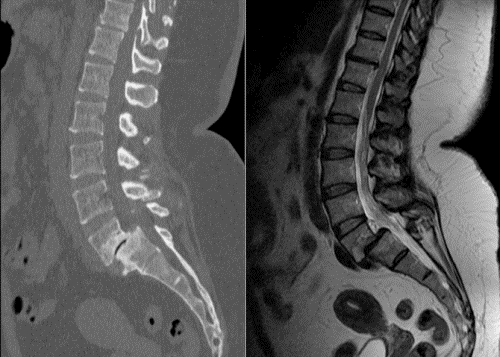

Лечение пациентов начинается с выявления причины болевого синдрома. При правосторонней люмбоишиалгии необходимо провести ряд исследований:

- рентгенографию;

- компьютерную томографию;

- магнитно-резонансную томографию;

Наиболее информативным методом диагностики является томография. На полученных изображениях можно обнаружить следующие изменения:

- остеофиты;

- смещение позвонков;

- истончение межпозвоночных дисков;

- грыжи;

- деструктивные изменения;

- переломы.

Магнитно-резонансная томография предоставляет более полную информацию, так как позволяет детально оценить состояние мягких тканей.